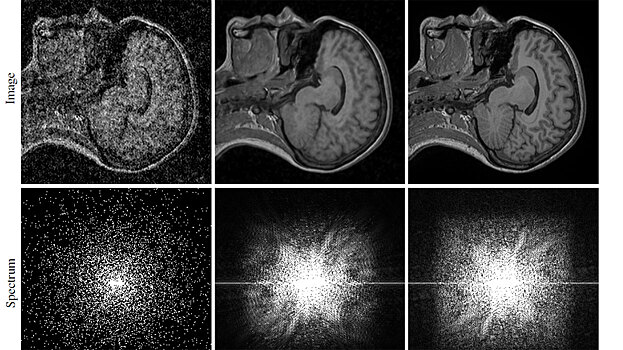

Cпециалисты компании Nvidia, Университета Аалто и Массачусетского технологического института создали нейросеть, которая улучшает качество фотографий почти без искажений. Новый метод был представлен на Международной конференции по машинному обучению ICML, которая проходила в Стокгольме (Швеция). Препринт статьи с подробным изложением нового метода исследователи разместили на arXiv.Org. В предыдущих подобных работах нейросеть обучалась восстанавливать фотографии, определяя разницу между парами изображений – с шумом и без. Новый метод отличается тем, что нейросети показывали только изображения с шумом. Тем не менее, она может устранять дефекты и автоматически улучшать качество фотографий. В начале работы над методом очистки изображений от шума исследователи добавляли на них гауссовский шум. Он характеризуется равномерной спектральной плотностью и нормально распределенным значением амплитуды помех. Всего в обучающей выборке было 50 000 изображений размером 256x256 пикселей. Работа с 30-слойной остаточной нейросетью RED30 привела специалистов к неожиданному выводу: они поняли, что использовать для обучения чистые изображения не нужно. Для дальнейших тестов исследователи использовали другую сверточную нейросеть — U-net, которая обучалась в десять раз быстрее при тех же результатах. В дальнейшем они добавляли на изображения другие виды шума — Пуассоновский, Бернулли и так далее. Все следующие тесты подтвердили, что гипотеза о том, что чистые изображения нейросети не нужны, верна. Созданный метод можно использовать не только для обычных фотографий, но и для улучшения МРТ-снимков или сделанных космическими телескопами изображений. Однако специалисты отмечают, что в их методе есть и минусы: например, нейросеть не может воссоздать объекты, которых не было в наборе тренировочных изображений. «Но это ограничение относится в равной степени и к обучению на основе чистых изображений», — тут же оговариваются ученые. Понравился материал? Добавьте Indicator.Ru в «Мои источники» Яндекс.Новостей и читайте нас чаще.